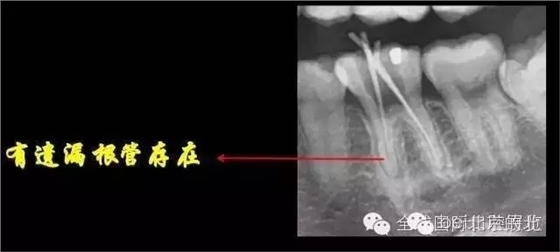

DB,DL.根管充填完成,樹脂封閉根管口,繼續(xù)探索未知的近中隱藏根管,所以決定拍1/4 CBCT確認MB存在, 其實預備的是MM和ML,

證實確實是遺漏了MB,

是遺漏了,但是又有新的問題出現,無法找到根管口,我一般會用8#Kfile去尋找根管,CBCT上看就在眼前,但是我就是看不到,也無法進入,此時操作也快一個小時了,患者也覺得累了,所以MB暫且停止尋找,因為也確實無法進入,所以把ML,MM根充完成,準確測量長度,AH-Plus,根管糊劑,涂布根管壁,冷牙膠依次充填完成暫封,下周繼續(xù)尋找失落的根管,同時也要把頰側楔缺的位置封閉好,防止再感染,再沒有橡皮障的保護下盡量減少感染機率。